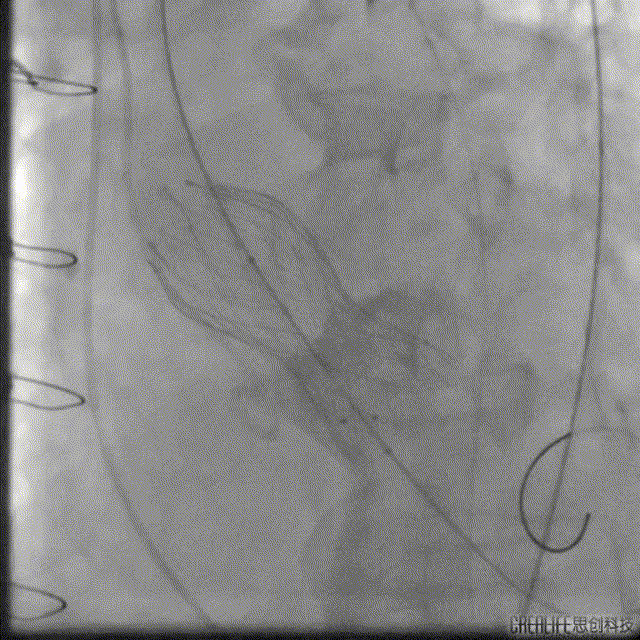

解剖上,这个患者虽然是右无融合的二叶瓣,但是右窦发育较小,形态上接近0型二叶瓣,瓣上钙化中,且集中在左窦,接近左右瓣叶联合部。瓣环及流出道平面较大,而瓣上结构较小,瓣叶联合部距离只有26,这种情况下只能考虑根据瓣上结构进行选择瓣膜。目标瓣膜为26号,为了避免破坏瓣上结构,我们选择26瓣膜的下限20号瓣膜进行与扩张。因为主动脉弓和升主动脉角度问题,没有选择plus。20球囊扩张可以看到左窦钙化很硬,右无联合可以推开,没有反流,故选择26号瓣膜,高位释放。释放后瓣膜下滑到标准位,有明显的腰,故用20球囊进行后扩展。最后造影虽然有中度瓣周漏,但是考虑患者狭窄解除,且升主动脉人工血管限制了瓣膜的流出端,未再行瓣中瓣。术中撤除ECMO,辅助循环约1小时。

术后:

患者跨瓣压差消失,轻中度瓣周漏,ECMO成功撤机后转入CCU,6天后转入普通病房,出院前超声显示EF值已提升为40%,患者症状改善,随后出院。